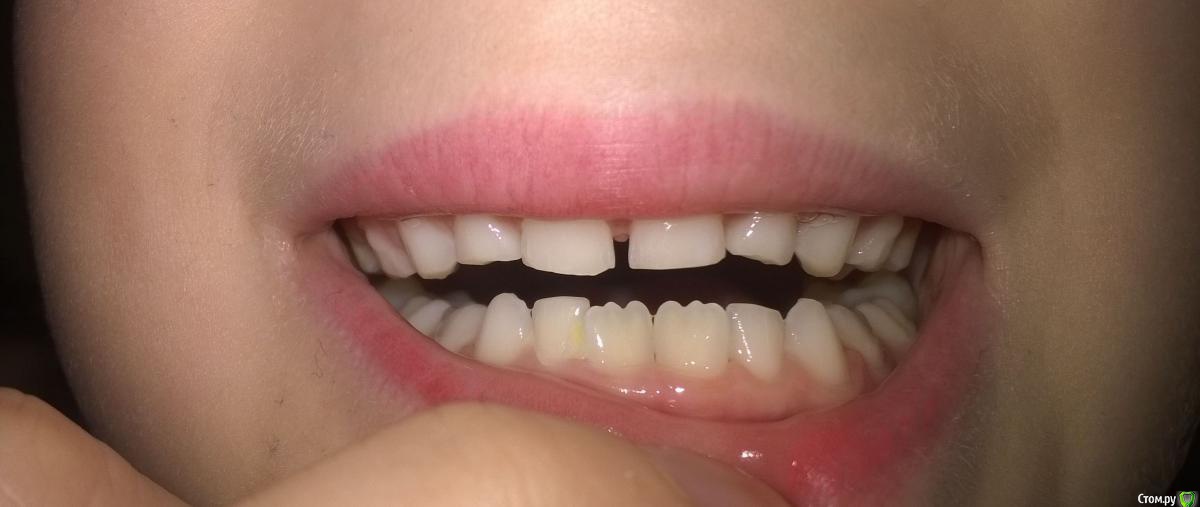

natashadmt Опубликовано 28 апреля, 2016 Автор Поделиться Опубликовано 28 апреля, 2016 Спасибо за советы. Сегодня были у доступного врача, он может предложить:1) по верхней челюсти: только вариант удаления 5го и установки пластины с 2мя винтами (расширяющий и выравнивающий зуб). Сказал, что корень 5го уже почти рассосался. Если шлифовать, то под винт места не будет и выровнять 6й все равно не удастся.2) по нижней челюсти расширяющую пластину с одним винтом Можете пояснить, как можно выровнять рост 6ки при сохранении 5го зуба? В чем плюсы минусы предложенного плана? Прикладываю еще несколько фото зубов. Ссылка на комментарий

Yana guapa Опубликовано 28 апреля, 2016 Поделиться Опубликовано 28 апреля, 2016 Можете пояснить, как можно выровнять рост 6ки при сохранении 5го зуба? В чем плюсы минусы предложенного плана? Прикладываю еще несколько фото зубов. http://i9.pixs.ru/thumbs/2/0/4/054b300x26_2123699_21734204.jpghttp://i9.pixs.ru/thumbs/2/0/5/1044a00jpg_9385611_21734205.jpghttp://i11.pixs.ru/thumbs/2/0/7/images2jpe_9068640_21734207.jpghttp://i9.pixs.ru/thumbs/2/0/8/images3jpe_9720062_21734208.jpg думаю по картинкам все понятно 2 Ссылка на комментарий